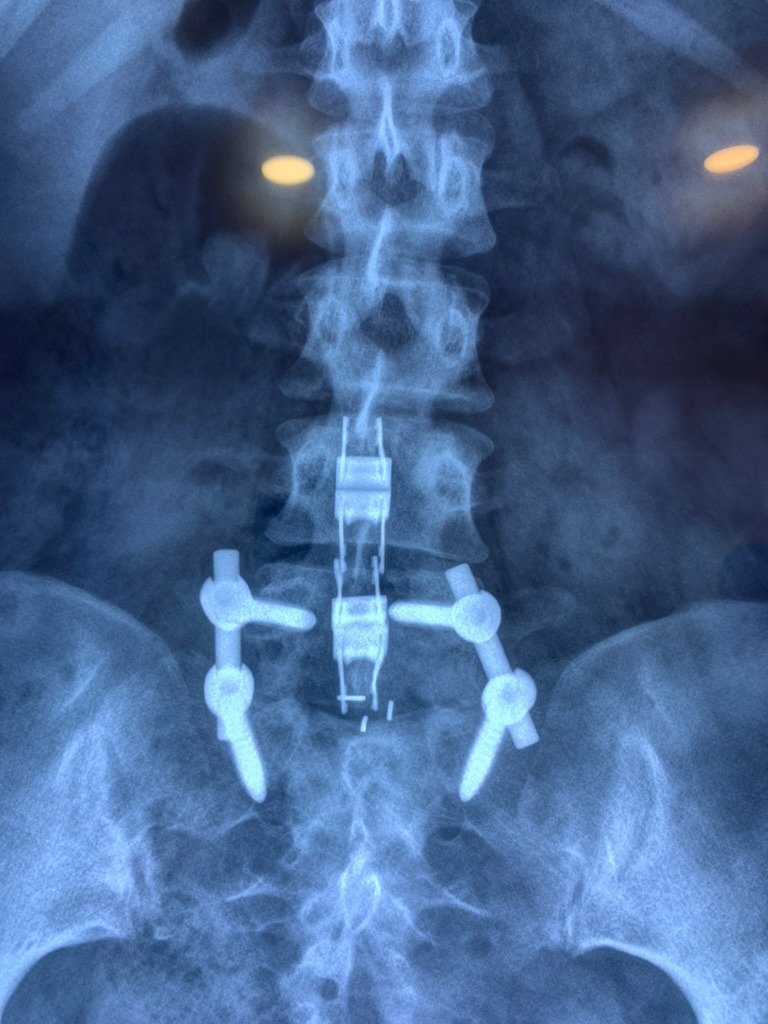

SURGERIES